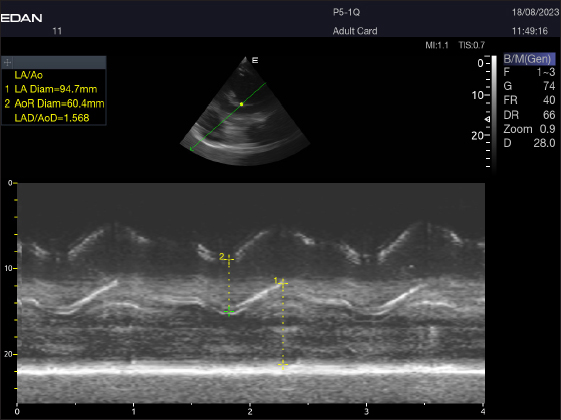

Right parasternal ultrasonography

By positioning the probe perpendicularly in the fourth intercostal space or longitudinally in the fifth space with a little clockwise rotation, the interventricular septum, ventricles, and atria could be observed in the caudal long-axis four-chamber view (Fig. 1). From this vantage point, all camels could be seen to have a left ventricle, mitral valve, interventricular septum, right ventricle, and tricuspid valve. Figure 2 shows that in the short-axis image of the cardiac ventricles obtained with a little clockwise rotation at the 4th ICS, only the right ventricle, interventricular septum, and left ventricle were visible. Here, the dimensions of all camel heart were measured in M mode. The right parasternal two-dimensional short-axis pictures of the heart’s base in the first frame were used to determine the LA/Ao ratio, by applying 2D and M mode (Figs. 3 and 4). Despite some difficulties, we successfully acquired a pulmonary image by attempting to acquire the right ventricular outflow tract for the right short axis at the level of the great vessels.

Fig. 4. LA/Ao ratios for the right parasternal short axis of 18 racing camels at the great vessel level. Through the anatomical M mode.

Echocardiography allows for the assessment of the heart’s dimensions as well as examination of its composition and operation. One of the most important ways to assess the severity and prognosis of cardiac disease in camels and cattle is to measure the ventricular chamber diameters (Holbrook et al., 2006; Buczinski, 2009; Tharwat et al., 2012). Dehghan et al. (2011) reported that the echocardiographic results of camels that were 1 year old were within the normal ranges. This is the first study to demonstrate the ability of adult racing camels to measure internal cardiac features and take heart images. As a result, it is better to conduct the camel’s ultrasonography examination when seated rather than standing (Tharwat et al., 2012). The short-axis view was technically simple, but Holbrook et al. 2006 claimed that it was technically challenging and had poor visualization because of pleural hyperechogenicity. In addition to probe size, compression of the thoracic intercostal spaces, and costal bone’s detrimental effect on the acquired images, other obstacles were encountered. Observed in cattle (Braun et al., 2001; Tharwat et al., 2012), the ultrasound images were of poor quality because the camel thoracic wall was thick, which attenuated the beam through absorption and reflection. All camels had little trouble obtaining the four-chamber view, which displays the atria, ventricles, and valves. However, because this study was conducted without sedation, unlike previous research (Braun et al., 2001; Tharwat et al., 2012), securing the camels required physical work. The cranial left and right parasternal long axis (five chamber view) is where the aortic valve is obtained, in contrast to Braun et al., 2001, who received the aorta from the right only. A right parasternal long-axis four-chamber picture was produced and aligned with Tharwat et al. 2012 after placing the probe in the fifth intercostal space.